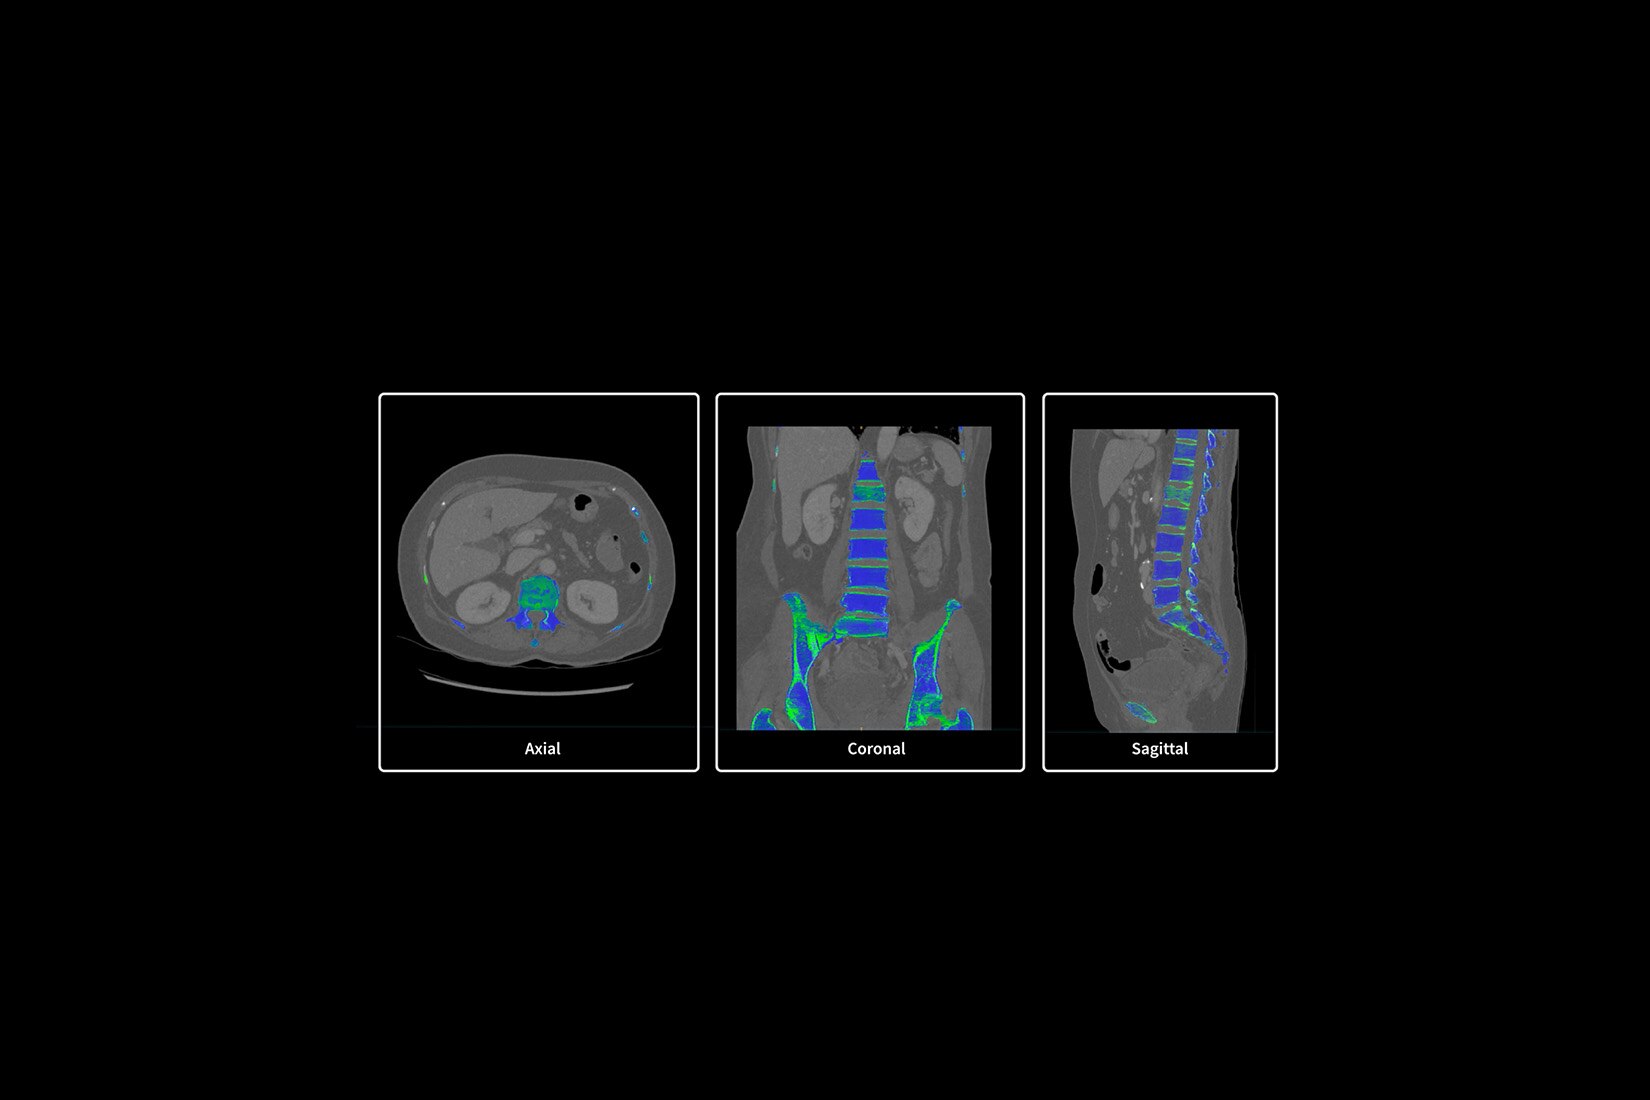

KLİNİK PERFORMANS

Klinik performansı yeniden tanımlıyoruz

BT deneyiminin en çok zaman alan kısmı taramanın kendisi değil; hastayı hazırlama, rekonstrüksiyon ve raporlama süresi gibi taramanın dışında kalan adımlardır. BT deneyimindeki tüm tarama öncesi ve tarama sonrası adımları analiz ettik ve önemli bulgularımızı Revolution Ascend'in tasarımına dahil ettik. Bu tasarımının sonucunda Revolution Ascend, yüksek BMI değerine sahip hastaları ve girişimsel prosedürleri verimli bir şekilde yönetebilme gibi yaygın endişeleri ortadan kaldırır. Ayrıca, tüm görüntüleme modları için kullanımı kolay iki düğmeli tarama sağlar.